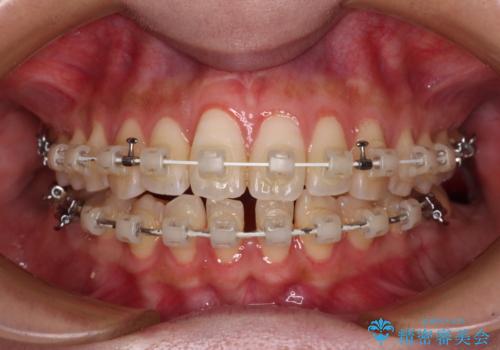

- 審美装置

周囲の歯を削らないようにするためインプラントがおすすめとなりますが、歯根の移動が不十分な場合にはインプラントを埋入する幅が獲得できないため、その場合にはオールセラミックブリッジにより補綴治療を行うこととして、矯正治療を行うこととしました。

当初は上記計画でしたが、レントゲン撮影よりインプラント埋入は困難と判断され、患者様と相談の上、歯を削ってブリッジとするよりも、奥歯の咬み合わせを多少妥協することとなっても、スペースを閉じて仕上げていくこととしました。